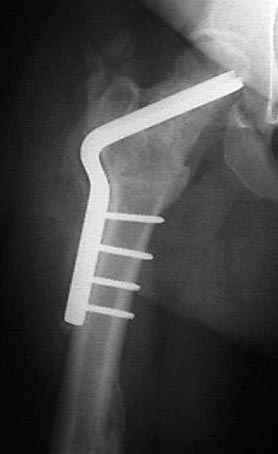

Если, например, доводится лечить больных с псевдартрозами шейки бедра, то надобность есть, и приходится. См. приложение.

На рисунке N1 предоперационный план лечения ложного сустава шейки бедра- линия ложного сустава, угол и направление введения импланта, клиновидная остеотомия в градусах и миллиметрах, второй снимок после коррекции, расчет, на сколько удлиняется конечность и размеры импланта;

N3 рисунок окончательный снимок, после операции моя рентгенограмма должен выглядеть примерно как эта картина. На N4 снимке клин перед удалением; N5 послеоперации 3 нед.; N6 окончательная рентгенограмма.